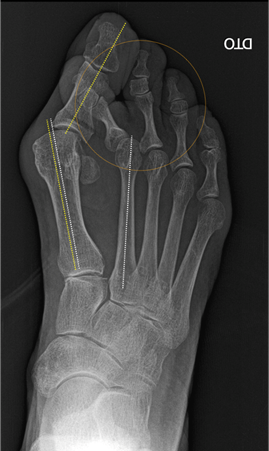

Ao exame objetivo para além de observar a deformidade anatómica do primeiro dedo, tem que ser avaliada a presença de outras patologias concomitantes como pé plano, metatarsalgia central, lesão da placa plantar, dedos em garra. É necessário avaliar a gravidade da deformação, a sua redutibilidade e avaliar o grau de mobilidade da articulação metatarsofalângica.

Geralmente o estudo é complementado com exames auxiliares de diagnóstico, como a radiografia dos pés em carga. Neste exame, é realizada a medição de certos ângulos, que irá orientar o tipo de tratamento mais adequado. Em casos selecionados poderá ser necessário a realização de TAC ou ressonância magnética.